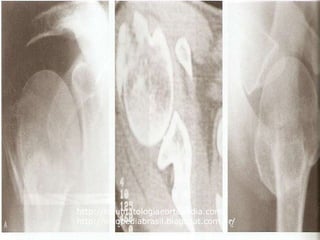

Complicações: • Necrose avascularda cabeça(0 a 71%) • Pode apresentar boa função do ombro • Colapso ou dor intolerável – substituição da cabeça (artroplastia total se artrose glenoidal) http://traumatologiaeortopedia.com/ http://ortopediabrasil.blogspot.com.br/

Necrose avascular após# 4 partes com boa função

Complicações: • Subluxação inferiortransitória – comum (hipotrofia muscular)Tto c/ tipóia + exercícios isométricos deltóide • Pseudo artrose(+ comum colo cirúrgico) • Infecção rara,geralmente relacionada a fios per cutâneos • Dor residual • Rigidez pós operatória